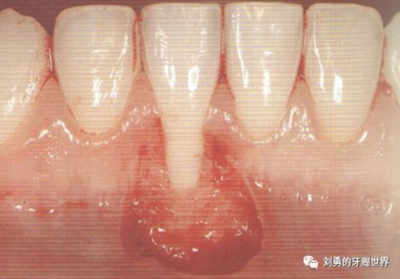

對(duì)于需要進(jìn)行根面覆蓋的手術(shù),移植瓣需要縫合固定到CEJ冠向1mm左右的位置。如下圖:

接下來我重點(diǎn)要介紹的就是該手術(shù)的各種改良的方法。